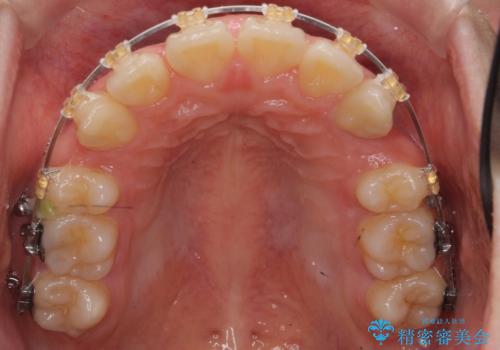

- 矯正装置

- 審美装置

上下左右の小臼歯を抜歯しています。